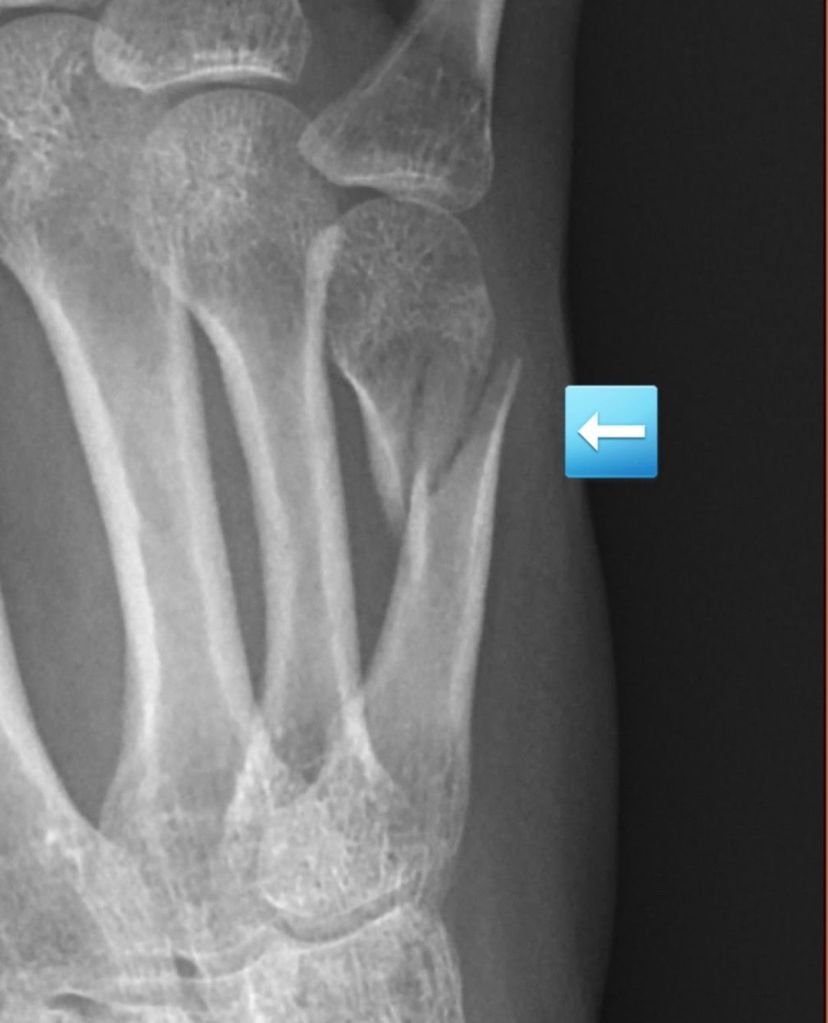

The x-ray confirmed a nondisplaced fracture of my fifth metacarpal, the bone in your hand that attaches to the pinky finger. I was bummed about not getting to use my new exerciser, but happy that the fracture was small and should have no issues healing.

A perk of my job is having a great work family. I walked to the orthopedic department next door and told one of the providers what was happening. They looked at the x-ray and agreed with the radiologist that it was a simple fracture. I was given a splint to wear. The fracture was so insignificant it did not even need to be put in a cast.

It was important to keep my fingers straight. However, the spasms were constantly hyperextending them. Then a new phenomenon started. After my fingers splayed out in unnatural positions after a spasm, they would snap closed into a clenched fist. I could not stop it. I had zero control over my own hand. The pain when my fingers closed would steal the air from my lungs as I gasped in both pain and surprise. I did not need an x-ray to know the fracture was worsening. The pain, my disfigured hand, and the continued bruising and swelling were enough.

Nevertheless, three weeks rolled around and it was time to take another x-ray. I looked at my coworker as he placed the lead apron over my lap and chest and told him I did not expect good news. He said it would be fine. We say that to all our patients. I knew better though. After the second image, he returned to the room shaking his head. “You’re right”, he said.

My nondisplaced fracture had completely shifted. If it had been a larger bone, it would have protruded from the skin. I went from an uncomplicated break that did not even need a cast to now needing surgery. My world crumbled. I was immediately terrified and overwhelmed with thoughts. My anxiety took control. I was afraid of the consequences of the anesthesia on my MS. I was terrified of not being able to use my hand for an extended period and whether I would ever regain strength and function. I was worried about the sick time I would have to blow through. I need that time for when I truly am disabled and can no longer work.